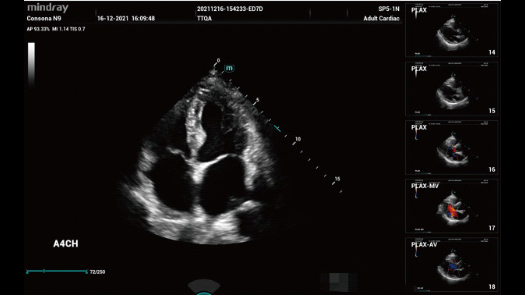

Dise?ado especĂficamente para usuarios de atenciĂłn primaria, el equipo Consona presenta soluciones nuevas y concretas que lo ayudan a realizar diagnĂłsticos sin problemas y de manera eficiente en diversos tipos de pacientes.

Independientemente de si lleva a cabo su rutina en hospitales o clĂnicas, o si estĂĄ perfeccionando sus habilidades en aplicaciones de diagnĂłstico por imĂĄgenes generales, atenciĂłn de la salud de la mujer o especialidades cardiovasculares, esta serie dispone de herramientas muy potentes para que se mantenga a la vanguardia.